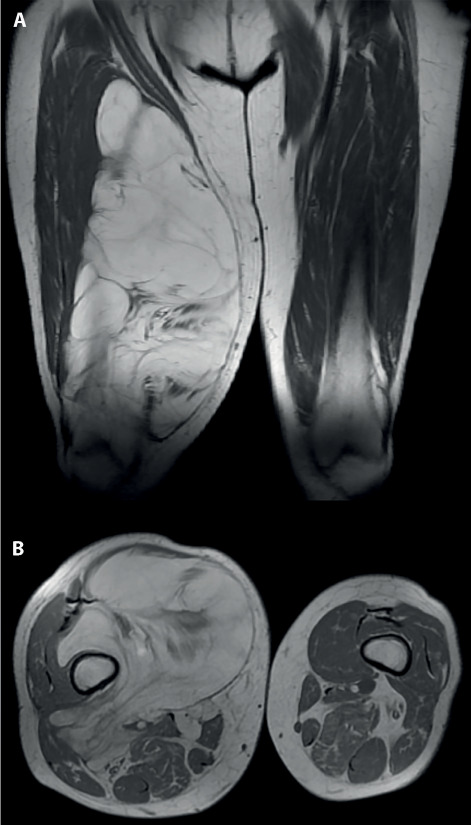

Background and aim: Atypical Lipomatous Tumors (ALTs) are low-grade locally aggressive soft tissue tumors. Deep large sized ALTs of the thigh can cause significant functional impairment due to their mass effect. Surgical resection, which is the treatment of choice for these lesions, can be a though procedure, especially if the neoplasm comes in proximity with noble structures such as large sized arteries or nerves. The aim of our study is to assess risks and effectiveness of surgical resection, evaluating complications, local recurrences and post-operative functionality.

Methods: We evaluated all the giant ALT (larger diameter of 10 cm or more) of the thigh that received surgery in our institution between 2017 and 2022. Each patient's personal data and tumor size were evaluated. The quality of surgical margins was analyzed. MRI scans were performed both pre-operatively and during patients' follow-up. Lower limb's functional status was assessed using the MSTS score before and after surgery. Intra-operative and post-operative complications were recorded, as well as local recurrences.

Results: Twentythree cases were included in our study. Tumors' mean major diameter was 19.1cm. The mean pre-operative MSTS score was 25.9. Only one case suffered from significant post-operative complications. Only 2 of our cases (8.7%) developed a local recurrence after surgery. The mean post-operative MSTS score was 29.1 Conclusions: A careful surgical resection can be effective in treating giant ALTs of the thigh in reason of good functional outcomes, low complications risks and reasonable local recurrence rates.